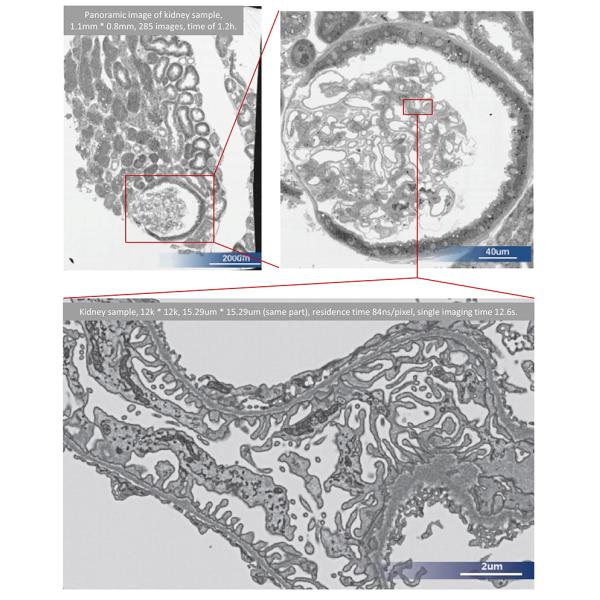

| Observe the microstructure of cells in mouse brain, heart, liver, kidney and other parts under scanning electron microscopy, and use Arrays Scan to perform fully automatic scanning on the target area samples of interest Intermittent matrix scanning, continuously capturing multiple high-resolution images. |

| Pathological Analysis Comprehensively collect all detailed information on the entire slice, and zoom in on any area to clearly observe the subcellular organelle ultrastructure on the kidney tissue |